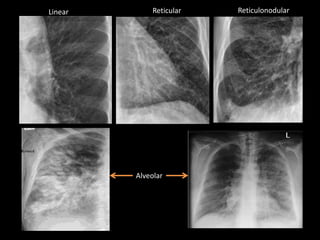

Linear Reticular Reticulonodular

Alveolar